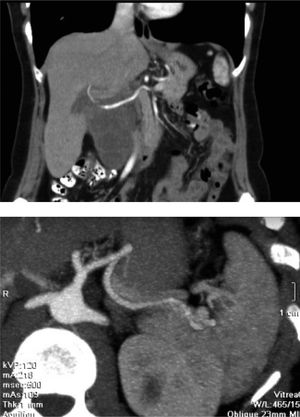

On abdominal ultrasound, a 10 cm multiloculated hepatic cyst was reported. A computed tomography scan (Figure 1) and a magnetic resonance imaging showed a multiloculated liver mass, involving the porta haepatis and extending to the IV duodenal portion. Additionally, endoscopic ultrasound confirmed the intrahepatic lesion involving the gastro-hepatic ligament and excluded a vascular compromise; the endoscopic ultrasound-guided fine-needle aspiration was compatible with a benign epithelial tumor.